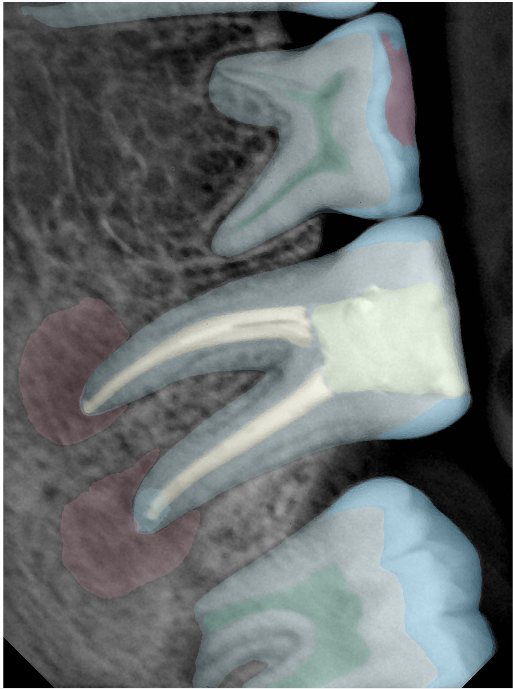

CR/DR 牙齿分割阶段记录

当前进展

- 完成了 CR/DR 牙齿相关分割训练

- 当前结果已经达到阶段预期,但仍有细节问题需要继续处理

相关测试

遇到的问题

- 训练过程中出现过 mask 下移问题

- 部分结果会出现 box 填充异常

- mask 边缘仍然有比较明显的锯齿感

参考

第二版算法问题测试